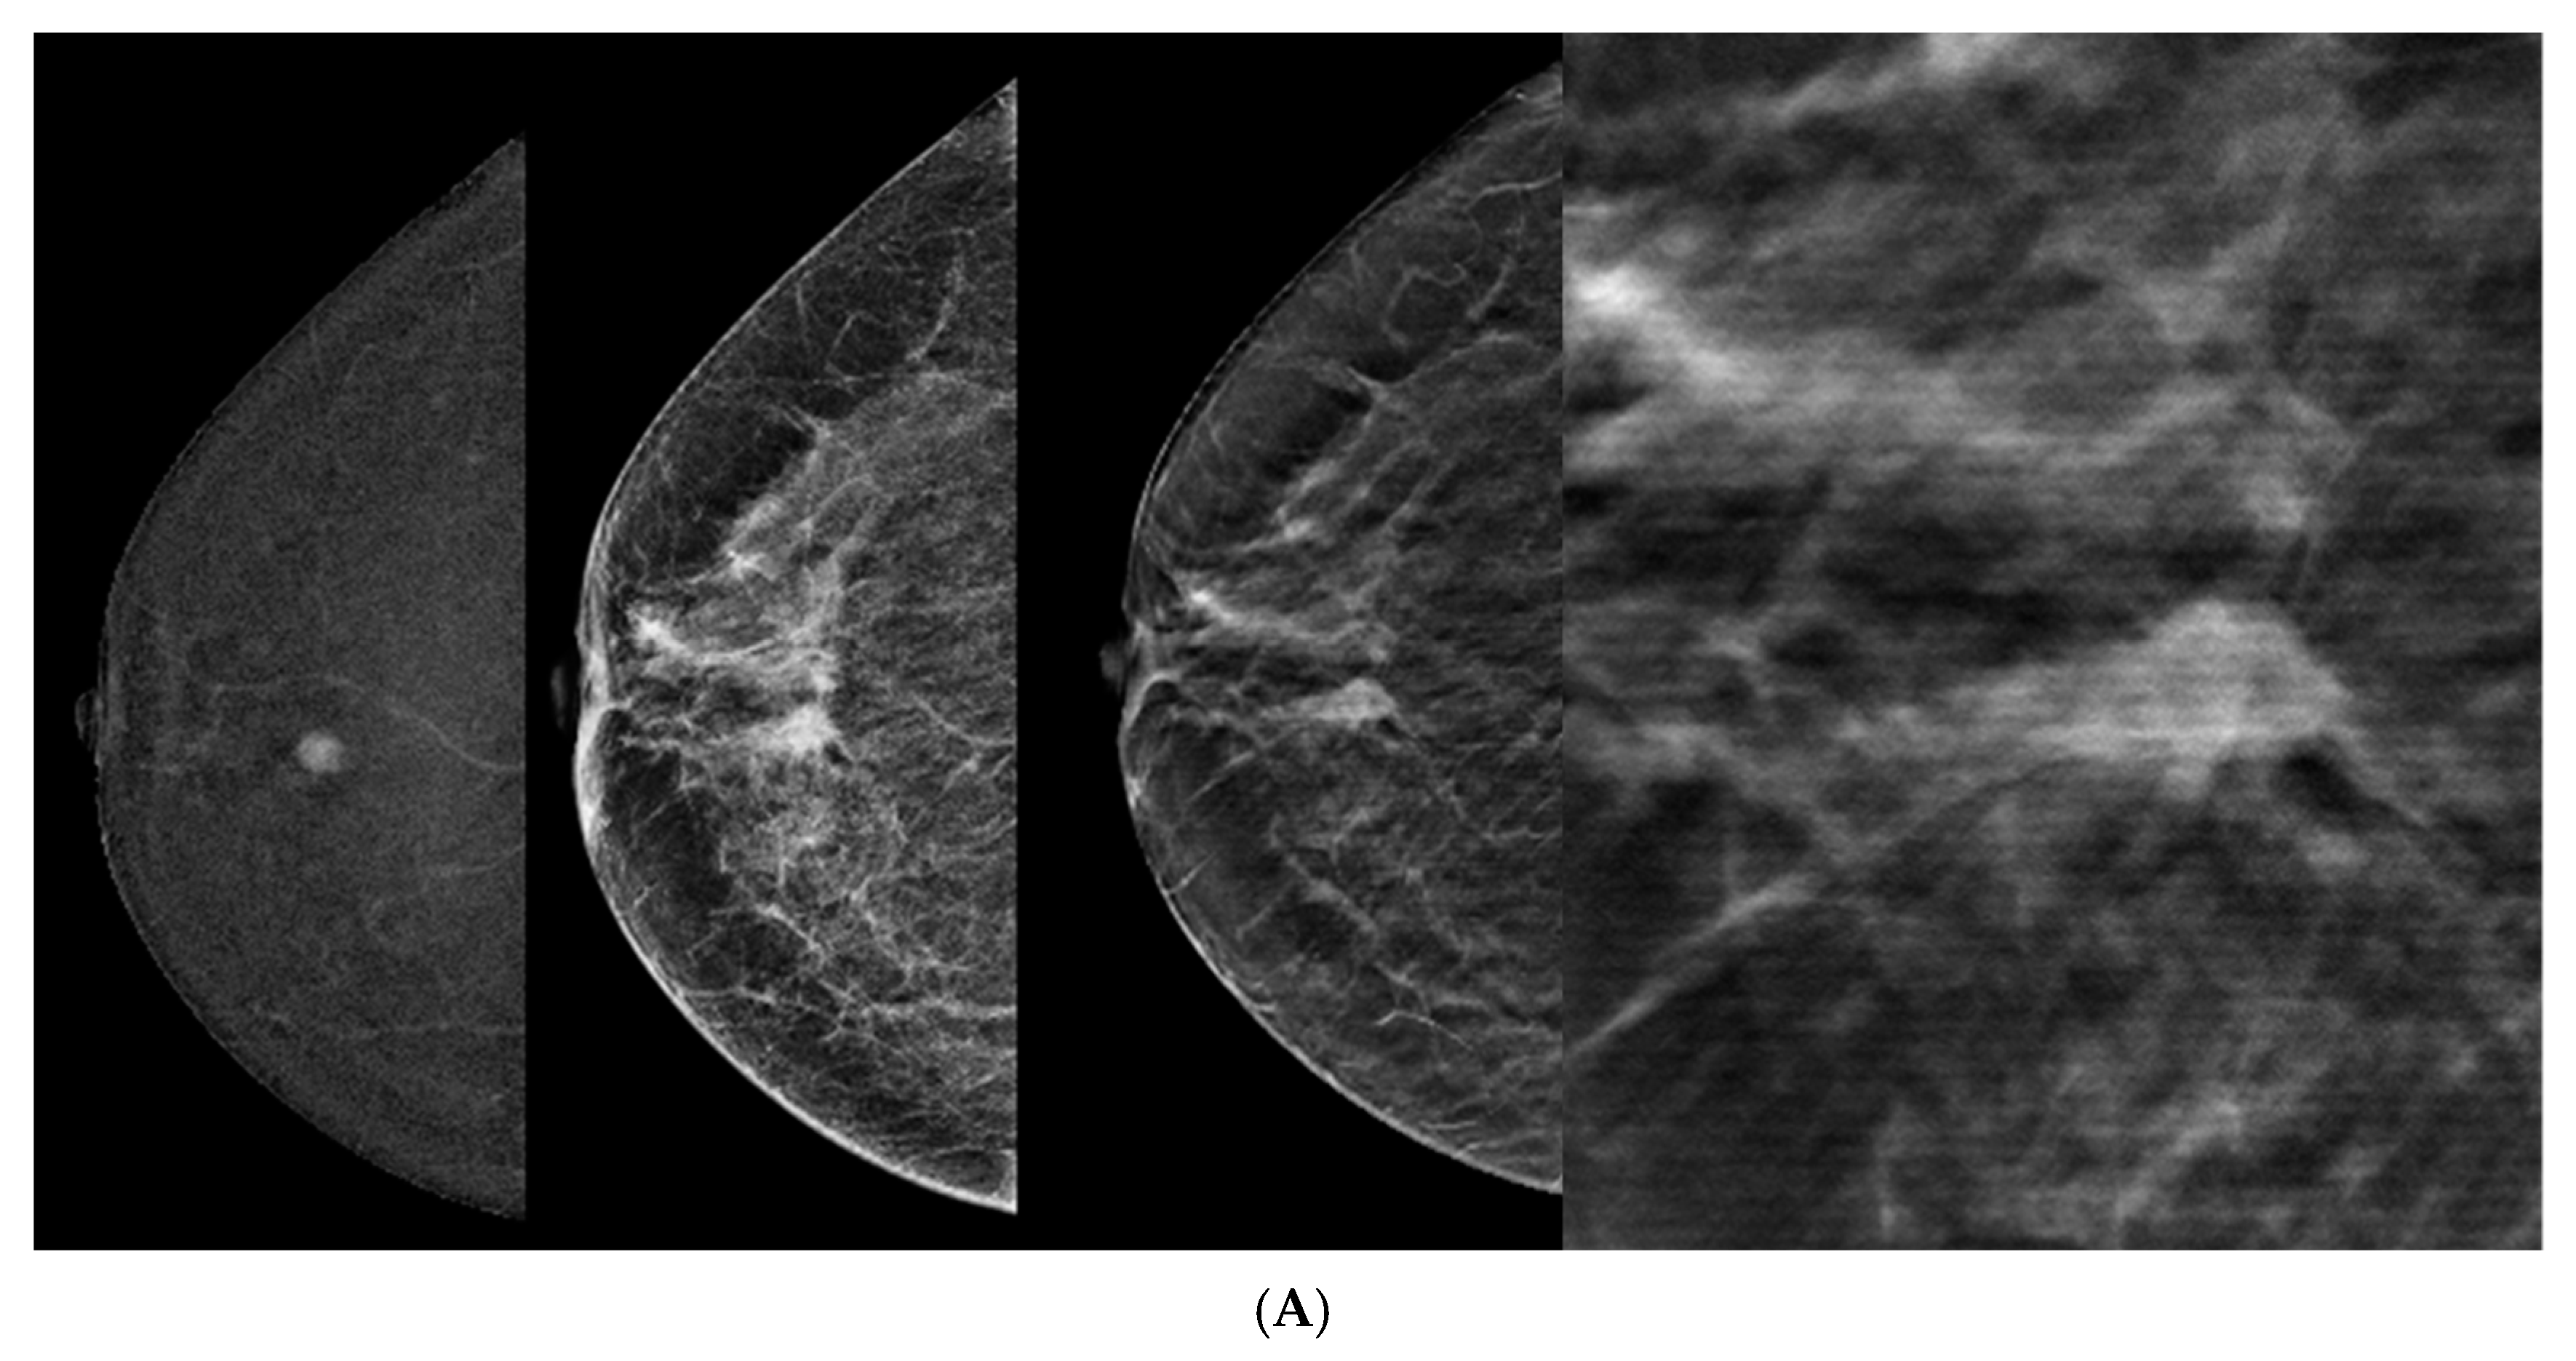

- Incorporating DBT into CEM-detected lesions leads to a significant upgrade in BIRADS scores toward the lesion’s true pathology (p > 0.0001).

- This was consistent across all readers, with particularly notable differences observed among less experienced readers.

- The primary driver for the score upgrade was attributed to improved margin visibility facilitated by DBT.